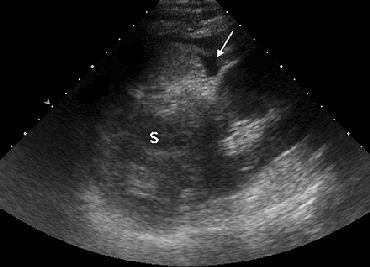

| A 22-year-old woman in the first trimester of pregnancy had sustained blunt abdominal trauma and subsequent splenic laceration in a motor vehicle collision. After US was performed, the patient was taken immediately to the operating room for laparotomy. Above, longitudinal US image of left upper quadrant reveals perisplenic free fluid (arrow) and abnormal-appearing splenic parenchyma (S). Below, longitudinal US image of pelvis shows free fluid (FF) superior to the bladder (BL) and gravid uterus (U). |

| Figure 3a-b, Richards JR, Ormsby EL, Romo MV, Gillen MA, McGahan JP, "Blunt Abdominal Injury in the Pregnant Patient: Detection with US" (Radiology, 2004; 233:463-470). |